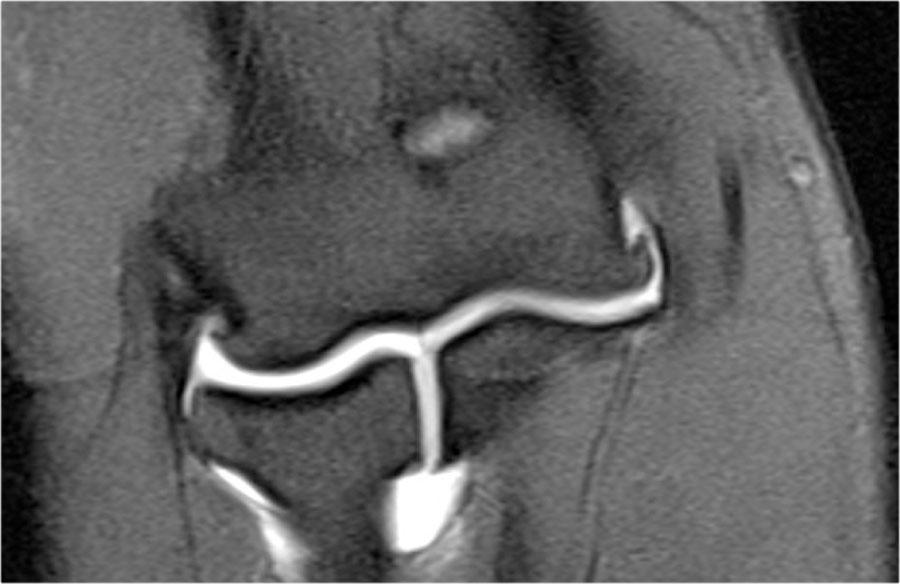

UCL repair

Sửa chữa dây chằng bên trụ (UCL) được thực hiện bằng cách tạo các đường hầm ở mỏm trên lồi cầu trong.

Các đường hầm chạy xuống đến củ sublime và một mảnh ghép được đặt vào giữa chúng.

Hình chụp X-quang này của một cầu thủ bóng chày chuyên nghiệp 26 tuổi đã được tái tạo dây chằng bên trụ (UCL).

Notice the tunnels (arrow).

Nếu bạn cuộn qua các hình ảnh MR, bạn có thể thấy đường hầm ở mỏm trên lồi cầu trong.

Giống như trong mảnh ghép ACL, chúng ta có thể thấy tín hiệu thấp của mảnh ghép kéo dài xuống phía dưới.

Trên các hình ảnh mặt phẳng coronal, mặc dù có các nhiễu ảnh dạng gai nhọn, dây chằng bên trụ (UCL) trông gần như bình thường.